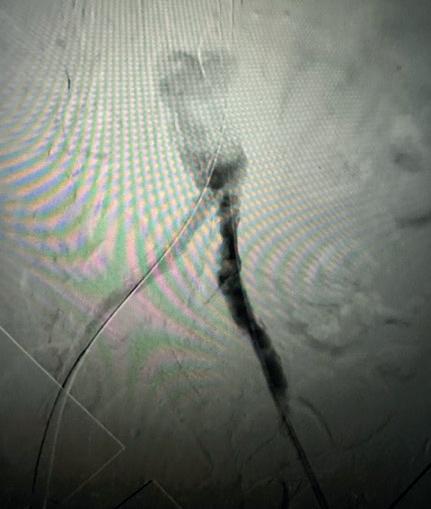

Case 2: The Shockwave M5+ tackles 90% stenosis of the distal SFA

The patient is a 75-year-old man with a history of hypertension, hyperlipidemia, CAD, chronic kidney disease and diabetes mellitus, who presents with a non-healing wound of the right lower extremity for three months.

He had undergone diagnostic work—his ankle-brachial index (ABI) was found to be 0.73 with a toe pressure of 50mmhg, and a duplex ultrasound revealed a densely calcified superficial femoral artery (SFA) stenosis of 90%.

He was taken to the cath lab and underwent a right lower-extremity arteriogram. This confirmed a 90% stenosis of the distal SFA, with normal three-vessel run off.

Due to the heavy calcium, we opted for a Shockwave M5+ 6x60mm and delivered 200 pulses to the lesion. There was no appreciable residual stenosis at the completion of the procedure, and his post-procedure ABI improved to 1.